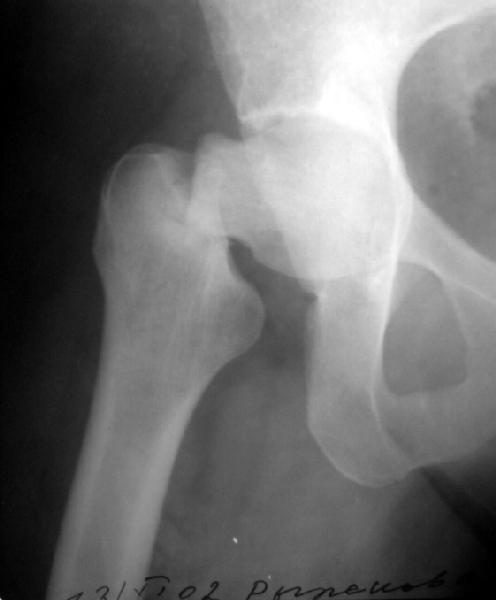

Женщина лет 40 переведена к нам из городской больницы с переломом шейки бедра.

Упала дома 5.11.02. С ее слов, в послдений год лечилась консервативно от якобы коксартроза с этой же стороны. Снимков не делали. Этот сустав болит последние несколько месяцев. На снимках обращает на себя "замыленность" краев. Не усталостный ли это перелом? Дама полноватая. Ограничения амплитуды движений до травмы она не отмечала. Мнения о тактике у нас разошлись в диапазоне от остеосинтеза винтами до эндопротезирования, с остеотомиями между ними. Помогите, пожалуйста, обосновать выбор.